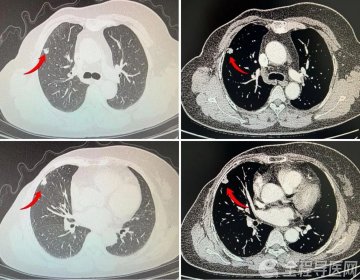

全程导医网 矿总频道:近期,徐州矿务集团总医院呼吸与危重症医学科马雷主任接诊了一位罹患典型多发性肺结节的患者。张女士(化名)今年55岁,一年前刚刚确诊乳腺癌,因乳腺恶性肿瘤行右乳切除,并在手术后接受了4个周期的化疗辅助治疗。住院期间患者胸部CT已显示存在一个大小约7mm的结节影,当时张女士并未选择干预肺结节,采取门诊随访。然而半个月前,张女士再次复查胸部CT时惊异地发现两肺均有多发性结节影,最大直径为13×7mm,结节较之前体积明显增大,数量增多,发展速度较快。

张女士的肺部病灶呈现出较为典型的多发性结节特征,结节影交错连结形成条块状,当务之急是需要高效高质的清理多个病变部位;然而另一方面,在接受了乳腺切除手术后,张女士的体质基础和心肺功能都相对较弱,对于再次切肺表示难以承受。

马雷主任通过与诊疗组其他专家的多方面讨论后,为尽可能改善患者手术体验、保障术后生活质量,让患者少受罪,又能精准定位肺部多发病灶,快速解除高危状态,他决定在一台消融术中安排两组消融针入路,分A线、B线;同时,进行冷冻肺活检穿刺取样,通过冷冻的方式降低出血,快速取样后病理送检。

张女士胸部CT显示,B组病灶由多个小结节连结成条块状。马雷主任选择首先定位至较深处的一个结节影,完成消融后往外退针,退针路径与其他病灶重合,一边退一边消,最终完成条状病灶的长段消融,并尽可能将创伤减小到最低。